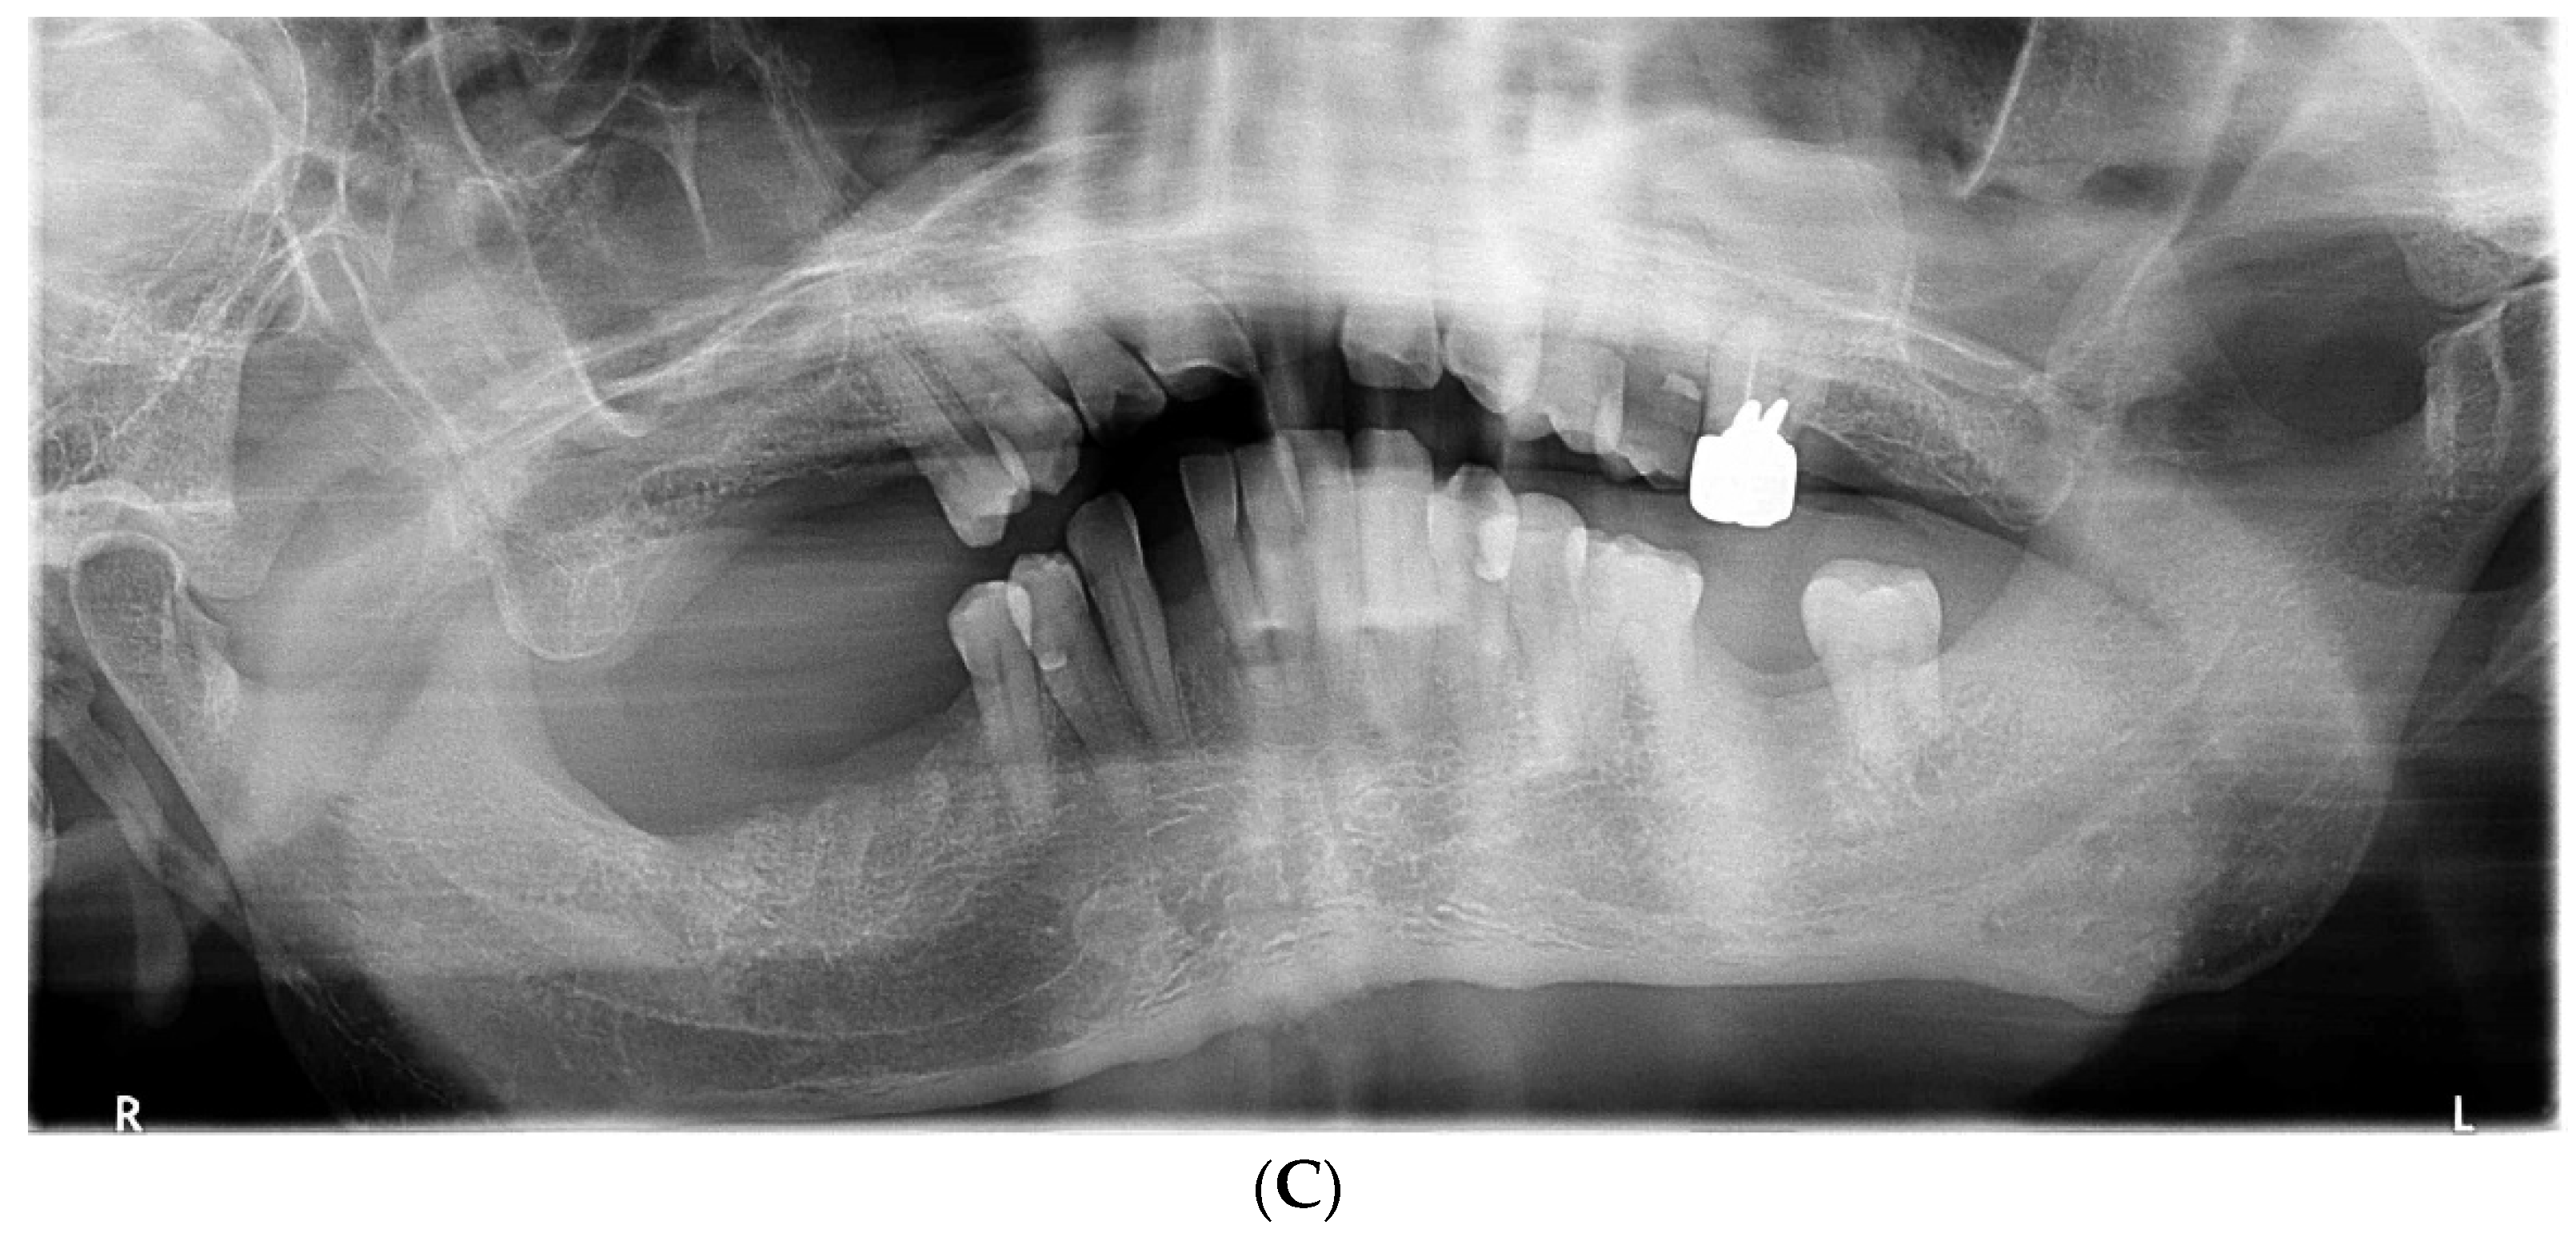

The acute symptoms resolved on day 7 (Figure 2A). We conducted a periodontal examination, including an assessment of probing pocket depth (PPD) and bleeding on probing (BOP). Because our patient had difficulty undergoing extensive examinations, we evaluated the one-point PPD instead of the six-point PPD (Figure 2B). Panoramic radiography was also performed (Figure 2C). During the periodontal examination, the entire circumference of each tooth was explored using the walking probe technique, and the value of the deepest pocket was recorded as representative of that tooth. In 11 teeth, PPD ≥ 4 mm with bleeding was detected. Of these, seven had deep pockets of >6 mm (Figure 2B). Panoramic radiography revealed a horizontal absorption of the entire alveolar bone (Figure 2C). On the basis of these comprehensive findings, NP was confirmed as the final diagnosis. Our patient also met the transiently and moderately compromised status criteria in the 2018 classification of NPD.

Figure 2.

The findings at 7 days after the first visit. (A) These intraoral photos show that the acute symptoms, including redness, swelling, and bleeding, have decreased. (B) Periodontal assessment includes tooth mobility (Mobility), bleeding of probing (BOP), and probing pocket depth (PPD) (maximum value on each tooth). Black color boxes indicate missing teeth. The green color box indicates acceptable PPD (not exceeding 3 mm). Yellow color boxes indicate PPD of 4 or 5 mm. Orange color boxes indicate PPD equal to or greater than 6 mm. BOP (−) indicates no bleeding. BOP (+) indicates bleeding. (C) Panoramic X-ray reveals that the entire alveolar bone has horizontal absorption.